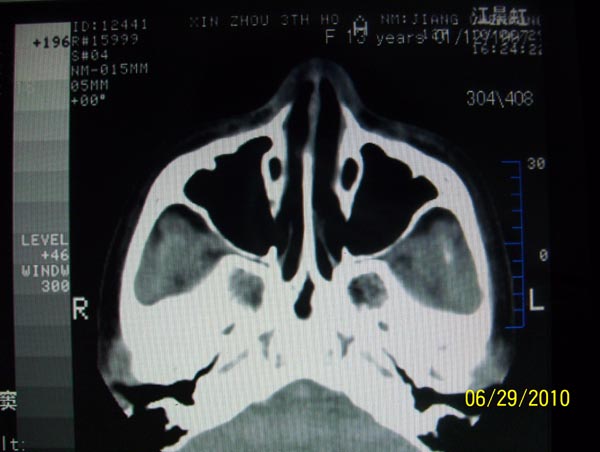

以下是引用随光逐影在2010-6-29 22:28:00的发言:[br]1)右侧下鼻甲肥大(或息肉样变)。2)鼻咽腺样体肥大。

以下是引用随光逐影在2010-6-29 22:28:00的发言:[br]1)右侧下鼻甲肥大(或息肉样变)。2)鼻咽腺样体肥大。

以下是引用随光逐影在2010-6-29 22:28:00的发言:[br]1)右侧下鼻甲肥大(或息肉样变)。2)鼻咽腺样体肥大。

以下是引用拾荒者在2010-6-30 19:22:00的发言:[br]右侧下鼻甲粘膜肥厚,鼻腔阻塞,鼻旁窦窦腔清晰,支持考虑慢性鼻炎。